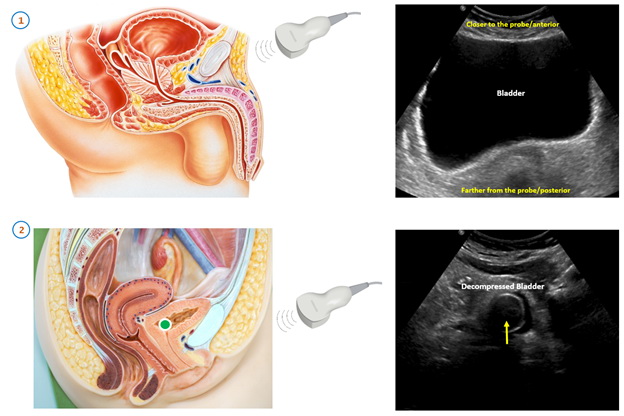

Трансабдоминальное УЗИ проводится лежа. Врач перемещает ультразвуковой датчик по нижней части живота, изменяя углы и направление, чтобы получить изображения мочевого пузыря с разных ракурсов. Во время процедуры врач может попросить пациента немного задержать дыхание или напрячь мышцы брюшного пресса, чтобы улучшить визуализацию.

Исследование проводится при наполненном мочевом пузыре. Заблаговременно до начала процедуры выпивается около 1 литра воды.  Не стоит стремиться к при слишком переполненному мочевому пузырю, так как результаты могут быть менее точными.